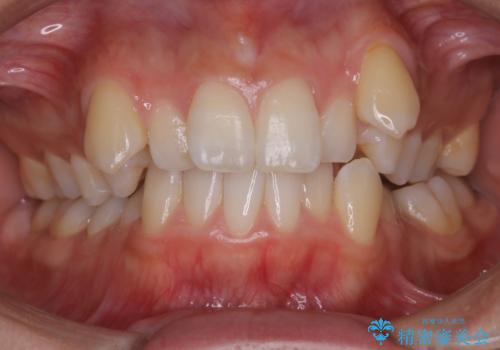

- 上顎の八重歯が気になるとのことで来院されました。

左側のかみ合わせは、歯1本分かみ合わせが前にずれていました。上顎左右の奥歯を2本抜歯しています。

八重歯でがたつきは重度でしたが、きれいな歯並びにすることができました。